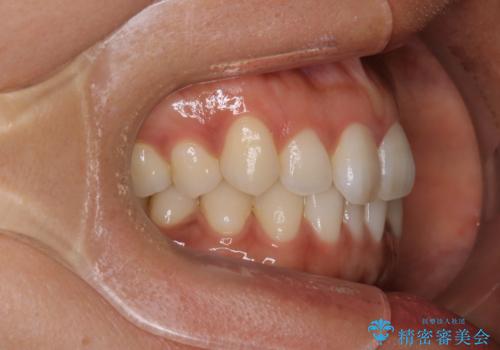

【インビザライン】前歯をきれいな歯並びにしたい

- 前歯の叢生を主訴に来院されました。このケースは抜歯をせずにIPRにてスペースを確保し、並べる計画をたてました。

きちんと使用時間を守って使用していただいたことで短い期間で治療が終了しました。